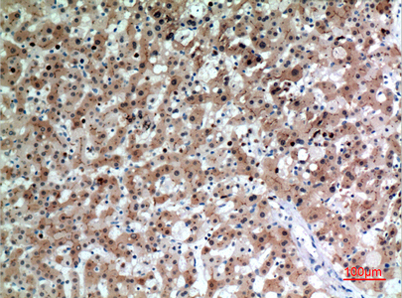

Product name: CD66e rabbit pAb

Alternative Names: CEACAM5; CEA; Carcinoembryonic antigen-related cell adhesion molecule 5; Carcinoembryonic antigen; CEA; Meconium antigen 100; CD66e

Dilutions: Western Blot: 1/500 - 1/2000. IHC-p: 1:100-300 ELISA: 1/20000. Not yet tested in other applications.

Immunogen: The antiserum was produced against synthesized peptide derived from the Internal region of human CEACAM5. AA range:481-530

Background: This gene encodes a cell surface glycoprotein that represents the founding member of the carcinoembryonic antigen (CEA) family of proteins. The encoded protein is used as a clinical biomarker for gastrointestinal cancers and may promote tumor development through its role as a cell adhesion molecule. Additionally, the encoded protein may regulate differentiation, apoptosis, and cell polarity. This gene is present in a CEA family gene cluster on chromosome 19. Alternative splicing results in multiple transcript variants. [provided by RefSeq, Jul 2015],